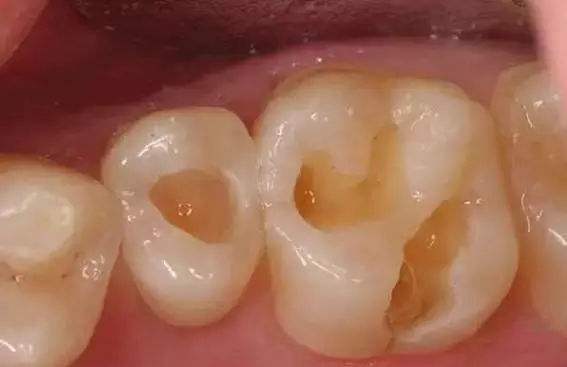

第一步,当患者来到医生面前的时候,医生首先需要根据患者的描述和自己的观察来判断牙齿的龋坏程度。

有的龋坏程度比较浅的,操作相对简单,如果龋坏比较深入已经接近牙神经,那这样的牙齿是不能轻易地说补就补的。

第二步,如果患者的牙齿龋坏程度不深,我们就要首先对牙齿龋坏的部分进行处理。

利用专门的机器将已经龋坏发黑的部分清理出来。这就是很多人困惑的磨牙洞的过程。因为如果我们不这么做,龋坏的部分还停留在牙齿上,看不见的细菌依旧存在。

只有将它们彻底去除了,同时将原本完全不规则的牙洞内部变的相对比较平整光滑,才更加有利于下一步的操作。